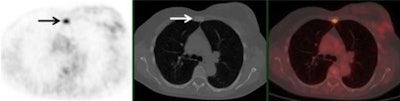

A 61-year-old woman with initial stage IIB triple-negative breast cancer was upgraded to stage IV. Axial PET, CT, and fused FDG-PET/CT show an FDG-avid osseous metastasis without CT correlate (arrows). A biopsy confirmed the metastasis. Image courtesy of Raychel Castillo and the SNMMI.Given the results, Castillo and colleagues concluded that FDG-PET/CT can be used as a diagnostic tool to find more advanced disease than in triple-negative breast cancer patients with stage II disease, thus slightly altering current NCCN guidelines.